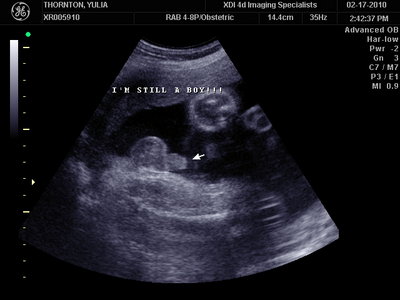

А это в 30 недель

| Вложения: |

MY BABY SONO!_20.JPG [ 94.63 КБ | Просмотров: 1083 ]

Sweetheart75 писал(а): Ну ладно, тогда и я нашего писюна покажу  Надеюсь, Джеффри на меня не обидится Вот это в 23 недели: (там оборудование переключалось из режима 3Д в обычный 2Д) Oоо, такое достоинство невозможно не заметить  А в 30 недель так вообще!